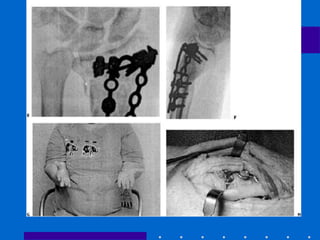

Fixação Externa

+ Redução aberta e fixação

interna

• Cominuição dorsal e volar de alta energia,

fragmentos não permitindo fixação interna

somente

• Varias coortes com sucesso

• Evita abordagem dupla dorsal e volar

• Figura 26-22